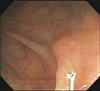

憩室症とは、腸壁にできる小さなポケットで(上図)、多くは無症状ですが、時には炎症を併発し、腹痛、発熱、出血等を来します(憩室炎)。 時には腸壁周囲に膿を作り(膿瘍といいます)、腸閉塞や穿孔等の由々しき事態になることもあります(左中下図)。

憩室症: 小さな穴(ポケット)が数個みられております(上)

憩室炎: 腸壁は赤く、腫れて、管腔は狭くなっております(中)

憩室周囲膿瘍: 憩室から膿が流出しております(下、重症例)